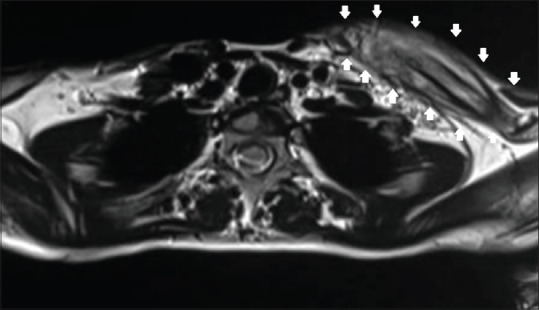

Figure 3.

MRI, T2-weighted (axial section) showing heterogeneous signal within the marrow and grossly thickened periosteum encircling the clavicle. The cortical outline is ill-defined at places